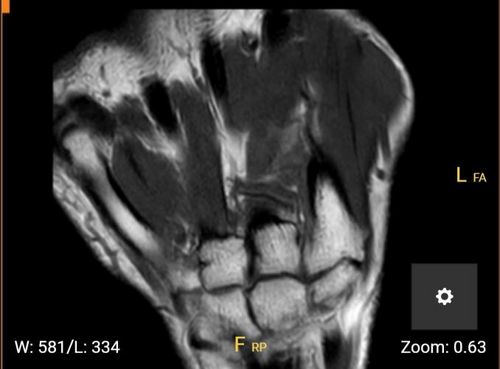

Der trianguläre fibrocartilaginären complex (TFCC) ist ein Bandkomplex mit einer knorpeligen Platte (Discus triangularis) in der Mitte.

Der TFCC dient als Puffer zwischen der Elle und den Handwurzelknochen.

Die TFCC Läsion befindet sich zwischen der Elle und den Handwurzelknochen.